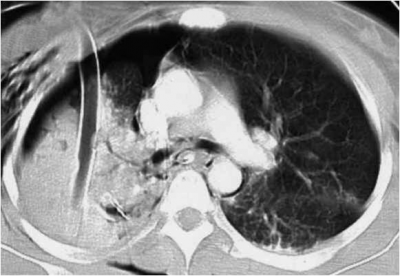

CT חזה היא בדיקה רגישה לחבלות ריאה ומראה שינויים כבר בשלבים מוקדמים ולכן ניתן גם להעריך את מידת הנזק לריאה ולעקוב אחר שינויים בריאה לטובה או לרעה (תצלום 17.16).